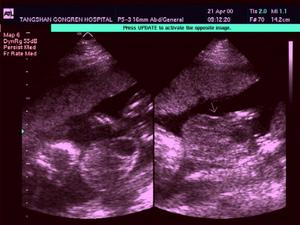

影像學檢查

1.平片:骨盆發育異常,恥骨聯合完全分開,分開的寬度約和骶骨寬度相當,使骨盆張開呈馬蹄形,兩股骨外鏇。

2.尿路造影:膀胱位置下降。